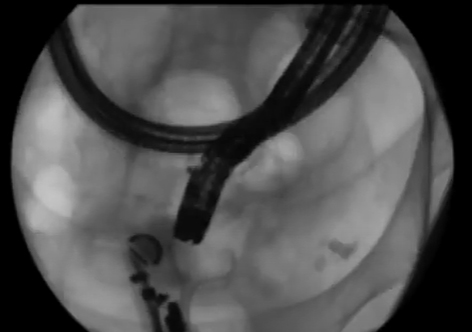

A pandemia de covid-19 reduziu em cerca de 60% o volume de colonoscopias, revela pesquisa feita pelo Hospital das Clínicas da Faculdade de Medicina de Ribeirão Preto da Universidade de São Paulo (USP). Autor da pesquisa, o proctologista Rogério Serafim Parra disse que isso ocorreu devido ao fechamento de alguns centros de endoscopia e à dificuldade dos pacientes para fazer os exames.… SAIBA MAIS